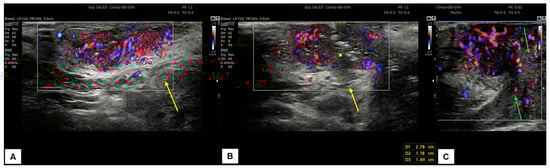

7.3. Malignant Vulvar Lesions

- Measurement from the adjacent most superficial dermal papilla to the deepest point of invasion

- Measurement from the basement membrane of the deepest adjacent dysplastic (tumor-free) rete ridge to the deepest point of invasion, which should be the technique of choice. Because epidermal ridges cannot be distinguished on ultrasonography, our suggestion is to take the lower hyperechogenic line of the epidermal layer as a reference (Figure 10).